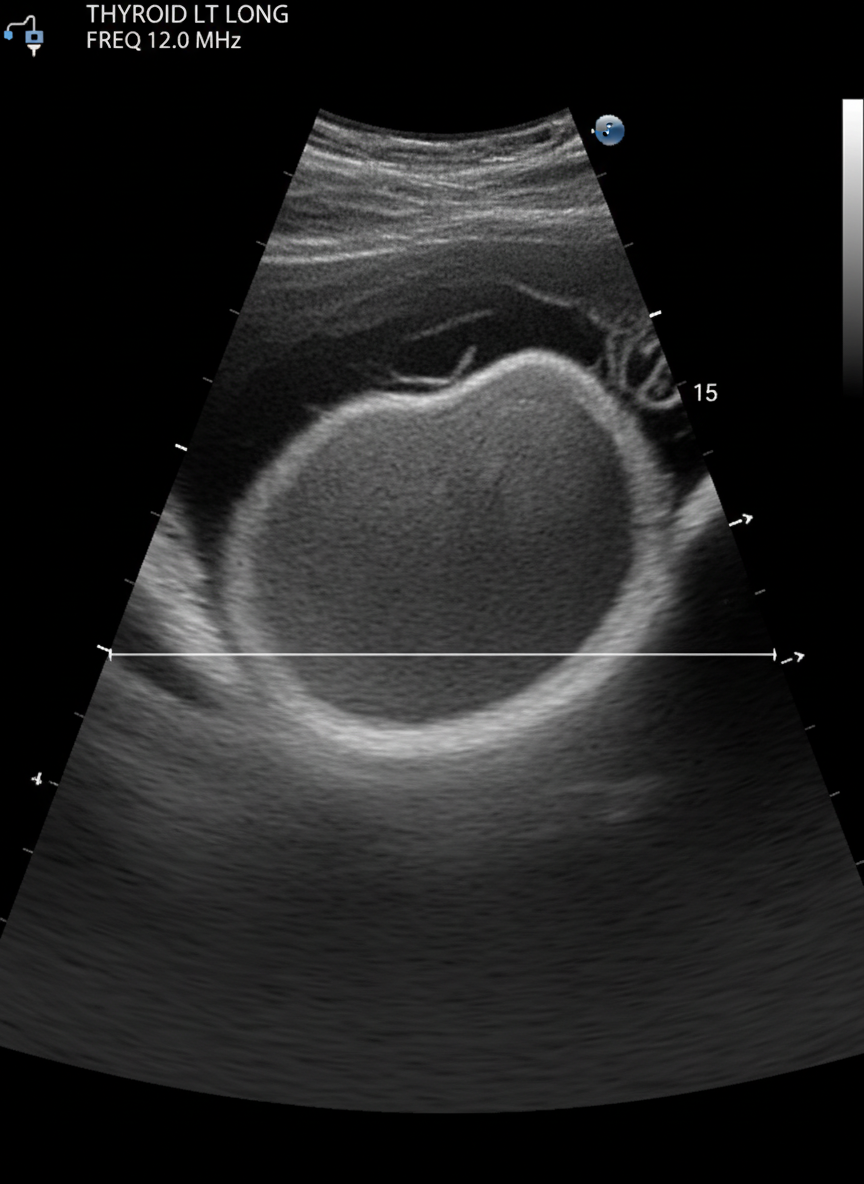

그 다음으로는 갑상선 초음파 검사를 하게 되는데,

이 초음파 검사를 통해

갑상선 결절의 유무와 크기, 모양 등을 확인할 수 있답니다.

초음파는 통증도 없고 아주 간단한 검사라서

부담 없이 받으실 수 있을 거예요.

만약 초음파 검사에서

의심스러운 결절이 발견된다면,

미세침 흡인 세포 검사(조직 검사)를 진행하게 돼요.

가는 바늘로 결절의 세포를 소량 채취해서

현미경으로 확인하는 검사인데,

이 검사를 통해 갑상선암 확진 여부를 판단하게 된답니다.